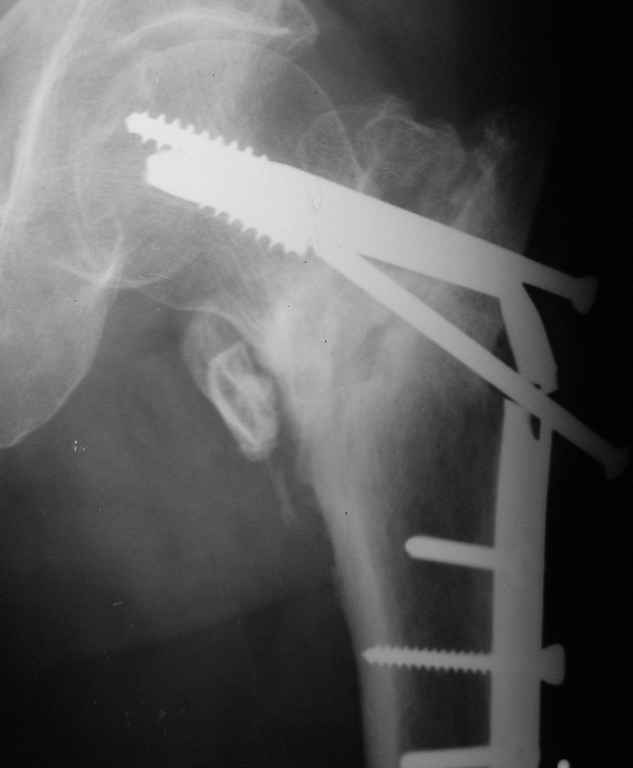

Сломанный спонгиозный винт, как достать??

Уважаемые коллеги!Подскажите пожалуйста, кто как и чем удаляет сломанные спонгиозные винты из шейки и головки бедра.

Сломанные винты удаляют специальным болтом из набора Broken Screw Removal Set от Synthes

Если нет необходимости дополнительных операций на шейке, тогда нет необходимости удаления.

Иногда, удаляя сломанные имплантаты, можно больше нанести вреда, особенно в головке бедра.